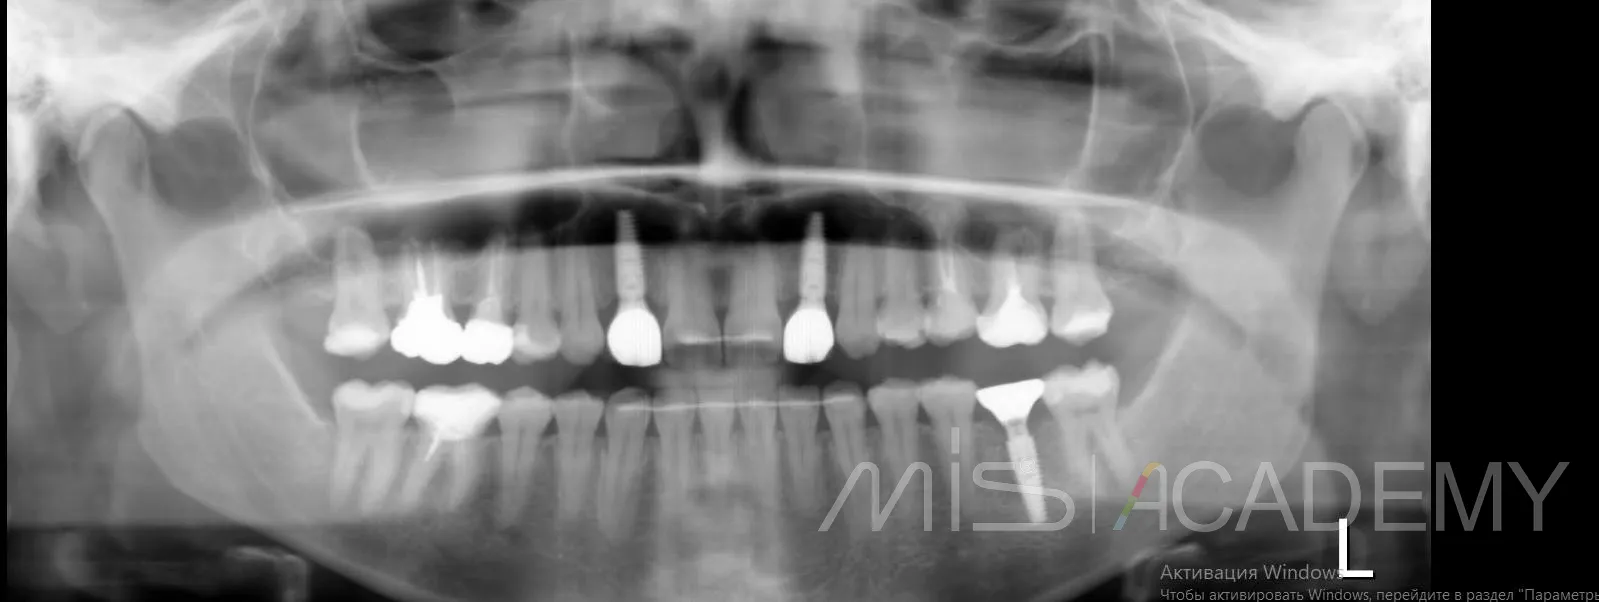

Небольшой рекол в 1 год после имплантации в область адентии двоек на верхней челюсти

— Имплантация MIS C1 узкая платформа.

— Connect абатменты.